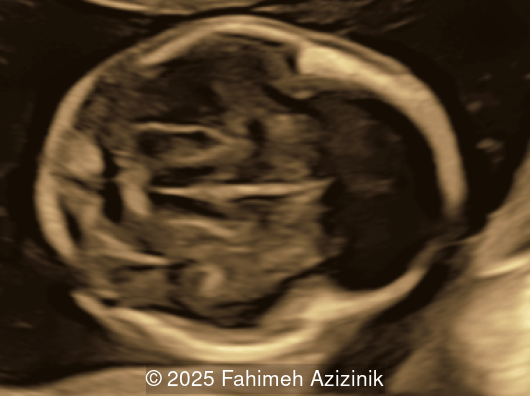

• Bicoronal craniosynostosis

Bicoronal synostosis is the characteristic cranial hallmark of Apert syndrome, detectable sonographically from 18 weeks. Its most recognizable manifestation is turribrachycephaly, defined by an elevated cephalic index (typically >85–90%) and a tall cranial vault with marked frontal bossing [19]. On prenatal ultrasound, the face in Apert syndrome shows midface hypoplasia with a depressed nasal bridge, proptosis, hypertelorism, and frontal bossing. The extremities demonstrate syndactyly of both bone and soft tissue of the hands and feet with partial-to-complete fusion often involving second, third, and fourth digits, known as “mitten hands” and “socked feet”. In severe cases, all digits are fused, with the presence of a single nail known as “synonychia” [20]. Other ultrasound findings include mild ventriculomegaly, agenesis of the corpus callosum, deficient or absent septum pellucidum, and fusion of the cervical vertebrae at the level of C5-C6 [21]. Cardiovascular (atrial and ventricular septal defect) and genitourinary anomalies (hydronephrosis, and cryptorchidia) are present in 10% of patients [22]. Increased nuchal translucency in the first trimester [23], widely open metopic suture [24], and polyhydramnios [25] have also been reported. Three-dimensional (3D) ultrasound facilitates assessment of surface abnormalities of the face and extremities, and magnetic resonance imaging (MRI) can be used to evaluate associated intracranial conditions [26].